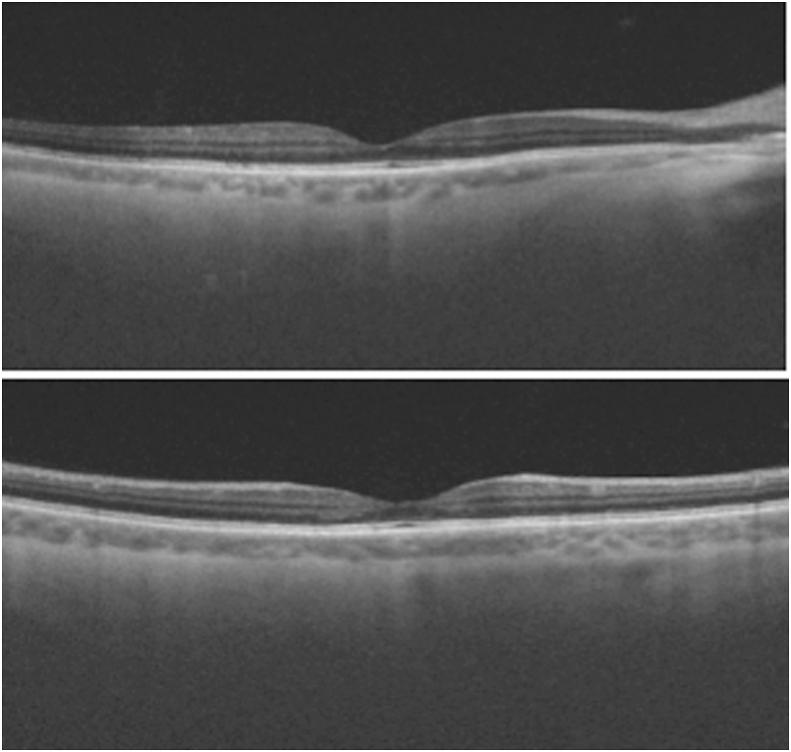

A 46-year-old man underwent a technically uneventful right eye phacoemulsification surgery using a standard dose (1mg/0.1mL) of cefuroxime solution injected into the anterior chamber at the end of the surgery. Serous macular edema and detachment were in our case observed on the first post-operative day. Without surgical intervention fast clinical recovery was observed and best corrected visual acuity improved to the final visual outcome of 1.0, which was satisfactory 10 days after surgery.

一名46岁男性接受了右眼白内障超声乳化手术,手术技术上顺利,在手术结束时向前房注射了标准剂量(1mg/0.1mL)的头孢呋辛溶液。在术后第一天观察到我们病例中的浆液性黄斑水肿和脱离。未经手术干预,观察到临床快速恢复,最佳矫正视力提高到最终视力1.0,术后10天效果满意。